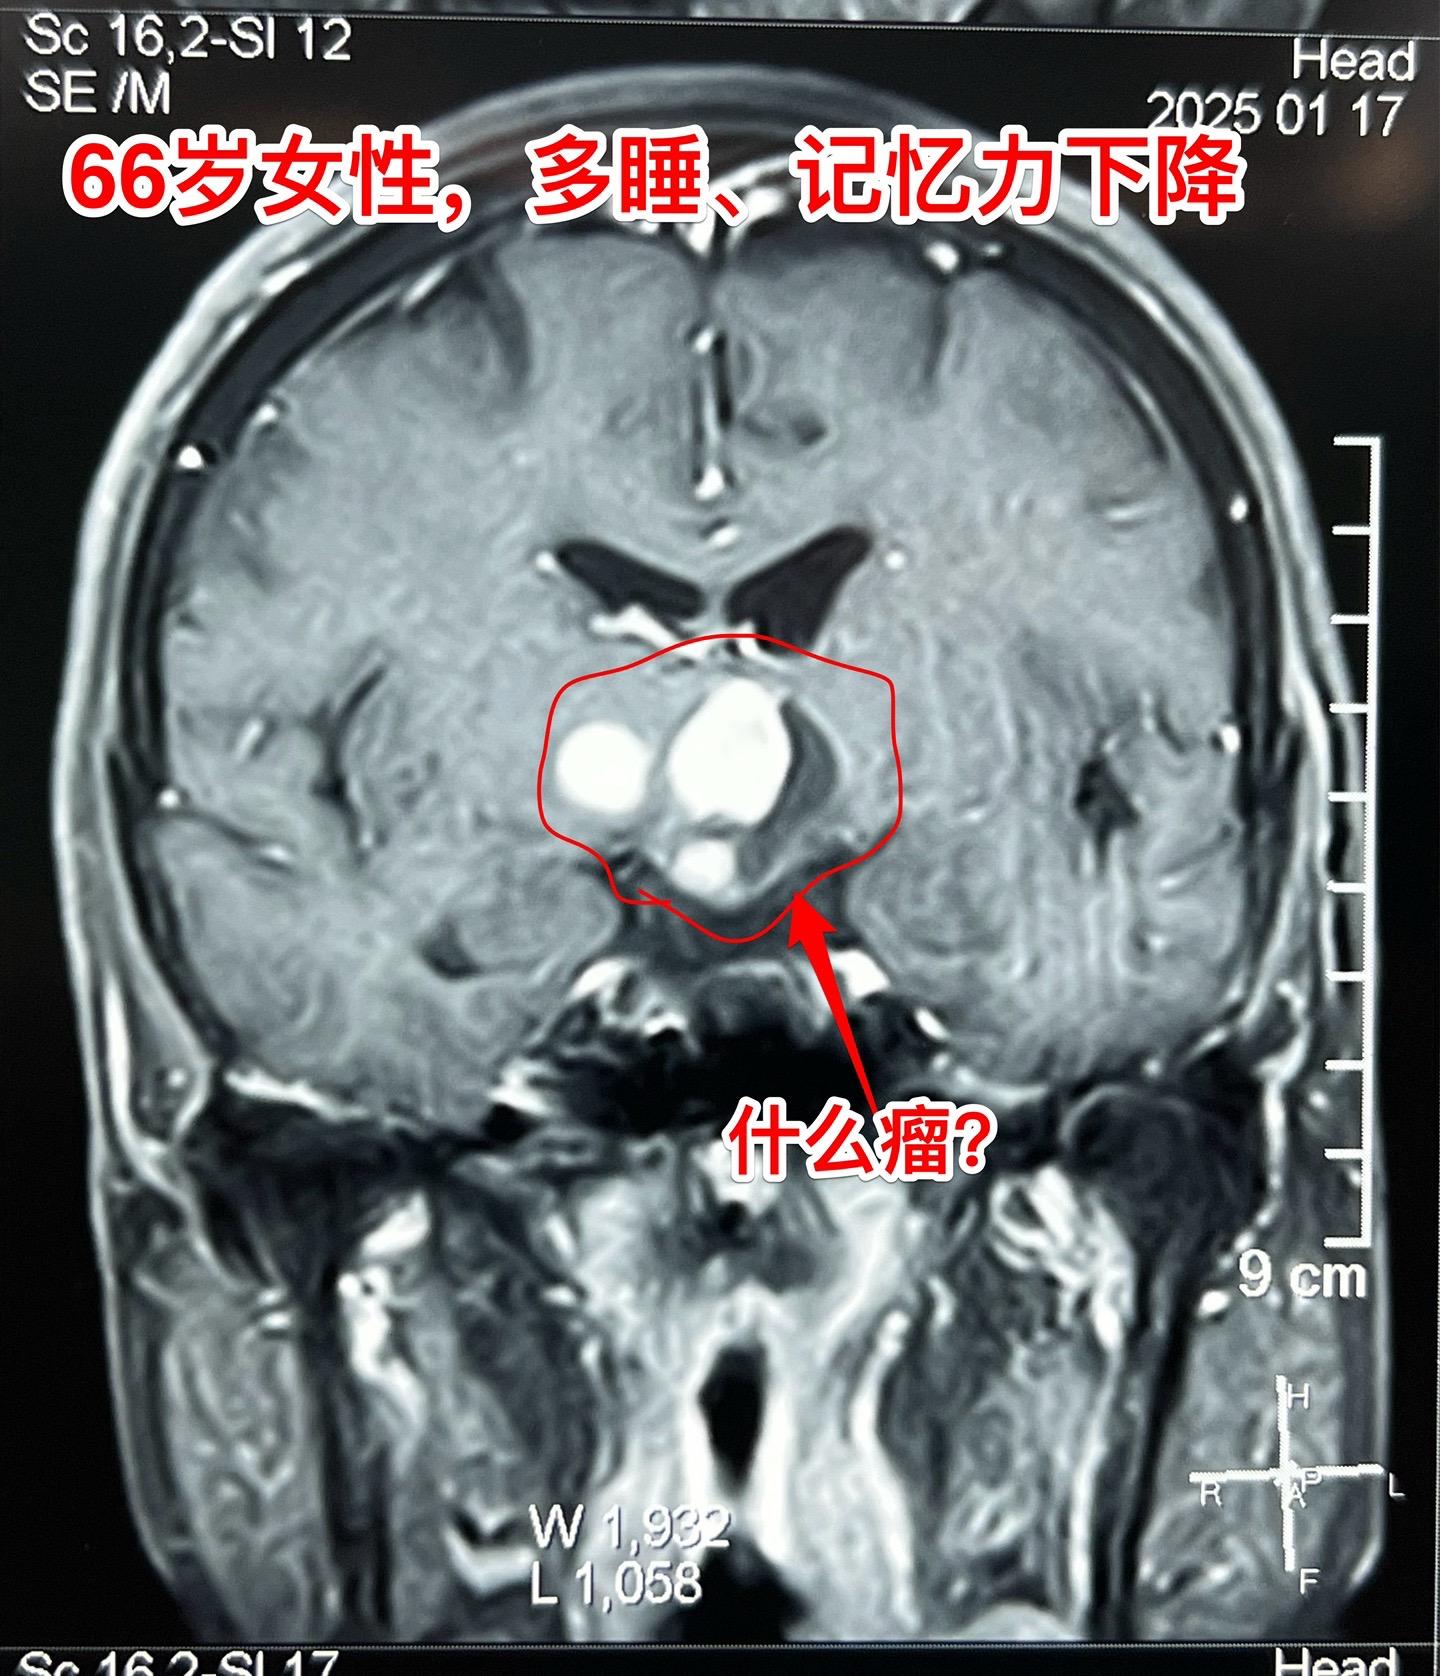

是颅咽管瘤吗?鞍区肿瘤的定性诊断是很难的。66岁女性,泰州人。因为多睡、记忆力下降在外院检查脑部发现脑部肿瘤。病人的多睡症状越来越严重。肿瘤位于鞍上区域,而且伴有脑积水。外院怀疑是颅咽管瘤?或者是别的肿瘤? 病人曾经在上海就医过,因担心手术风险,通过三博脑科医院院长找我咨询,随后决定到我院作手术。 1月24日作了开颅手术(这是我科春节前的最后一个择期手术),手术中发现肿瘤的性状不符合乳头型颅咽管瘤,分两次取标本送快速冰冻病理检查,报告考虑是胶质瘤。 下丘脑胶质